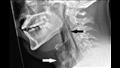

في حالة طبية نادرة، أصيب رجل في الثلاثينيات من عمره بتمزق في القصبة الهوائية بعد محاولته كتم العطس.

تم نقل الرجل إلى مستشفى ناينويلز في دندي، اسكتلندا، وهو يعاني من آلام شديدة في الحلق، بعد كتم العطس أثناء القيادة.

أخبر الأطباء أنه كان يعاني من نوبة من حمى القش، وعندما شعر بالرغبة في العطس، قام بحبسها عن طريق الضغط على أنفه وإغلاق فمه.

قال الدكتور راسادس ميسيروفس، من مستشفى ناينويلز، بحسل موقع central oddity، إن محاولة كتم العطس يمكن أن تكون خطرة. "عندما تفعل شيئًا كهذا، يمكن أن يزيد الضغط في مجرى الهواء العلوي بنحو 20 مرة، مما قد يؤدي إلى إصابات خطيرة بما في ذلك تمزق طبلة الأذن، وتمدد الأوعية الدموية، وحتى كسر الأضلاع."

في هذه الحالة، انتهى الأمر بالرجل بتمزق 2 ملم في القصبة الهوائية، وهي الأنبوب الذي ينقل الهواء من الأنف إلى الرئتين. تمزق الحلق، المعروف طبيًا باسم "الثقب الرغامي التلقائي"، هو إصابة نادرة وربما تهدد الحياة ولم تكن مرتبطة بالعطس الخانق من قبل.

خرج الرجل من المستشفى بعد بضعة أيام مع مسكنات للألم وأدوية لحمى القش. وبعد خمسة أسابيع، عاد لإجراء فحص طبي ووجد الفحص أن التمزق قد شفي.

وقال ميسيروفس: "يجب أن نغطي الوجه بلطف إما بأيدينا أو بالجانب الداخلي من المرفق لمنع وصول المهيجات مثل الفيروسات واللعاب والمخاط إلى الآخرين من حولنا، ويجب ترك الممرات الأنفية مفتوحة.